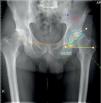

Sexto pasoSe traza la línea bilacrimal (sobre la base de las 2 imágenes en lágrima de Köhler) con el fin de orientar el eje pélvico transversal y tener un patrón de referencia para comparar la longitud de los miembros inferiores. Si no se identifican dichas imágenes en lágrima, se pueden utilizar las tuberosidades isquiáticas o los agujeros obturadores aunque, en estos casos, la medición podría resultar menos exacta, en función de la calidad de la proyección radiográfica. Este eje transversal sirve para calcular el ángulo deseado de inclinación (o abducción) del componente cotiloideo, colocando la plantilla del implante en una adecuada posición con respecto a la pelvis y al trasfondo acetabular (fig. 3). Al mismo tiempo, también se determina la talla del cotilo.

Planificación del componente cotiloideo (ajuste de talla y ángulo de inclinación). El eje transversal sirve para calcular el ángulo deseado de inclinación (o abducción) del componente, colocando la plantilla del implante en una adecuada posición con respecto a la pelvis y al trasfondo acetabular.